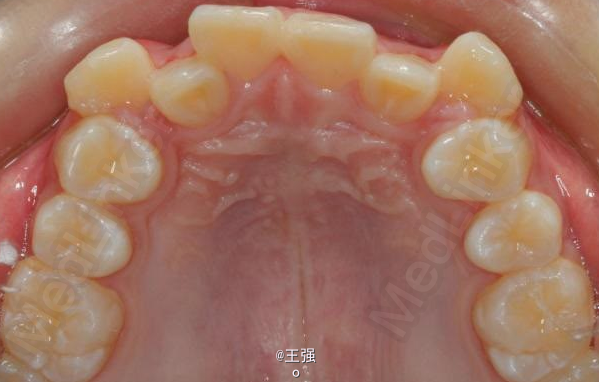

在临床上,我们常常会遇到亚类病例,对于亚类病例,有时需要不对称拔牙,常见的不对称拔牙方法有:上颌对称,下颌数目对称但是位置不对称。还有上颌对称,但是下颌数目不对称。其目的就是为了取得尽可能理想的尖窝对应咬合关系 该病例右侧是中性关系,左侧是中性偏远中关系,上颌中线正,下颌中线左偏约1mm。左侧磨牙关系距离中性关系约差2mm左右。如果采用对称性拔除下颌左右四,我们面临的问题是,一、如何保证矫治后上下中线一致,二、如何保证左侧磨牙关系矫治后为中性关系。治疗过程中势必会用到不对称牵引。我个人认为除非是功能性的因素,矫治过程中最好不要用不对称牵引。 关于中线和磨牙关系的问题,我认为应在矫治计划制定时就应考虑到,而不是等到矫治第三阶段所谓精细调整阶段再来解决。事实上到了这个阶段采用了不对称的牵引,即使暂时取得了中线对齐的矫治目的也是不稳定的。 这个病例,用了不对称的拔牙,右下拔四,左下拔五。下颌牙齿在漂移的过程中(几乎没有外来力量),下前牙自然就会向右比向左多漂移一些,中线在下颌还没有开始矫治时就对齐了,左下六因没有五的存在,自然就向近中多漂移一些,和上颌六形成中性关系。接下来的矫治就会非常简单,而结果自然也非常稳定。